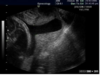

What pathology does this depict? [1]

Placenta praevia Fig 3 – Anterior placenta previa. The placenta (arrow) has covered the internal os completely (arrowhead).